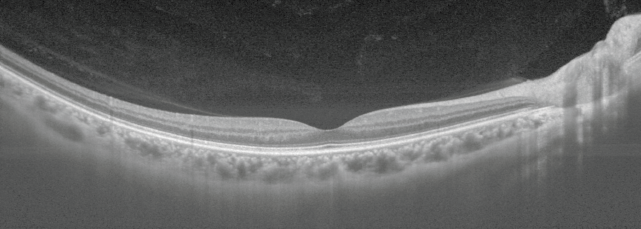

JASEN PREGLED DEBELIN MREŽNICE IN ŽILNICE

IMAGEnet7 omogoča do 5 zemljevidov debeline mrežnice, kar omogoča kvantifikacijo mrežnične plasti in podplasti.

Triton2 zagotavlja jasno vizualizacijo žilnice in ustvarja zemljevide debeline žilnice, kar podpira klinično razumevanje strukturnih sprememb žilnice.